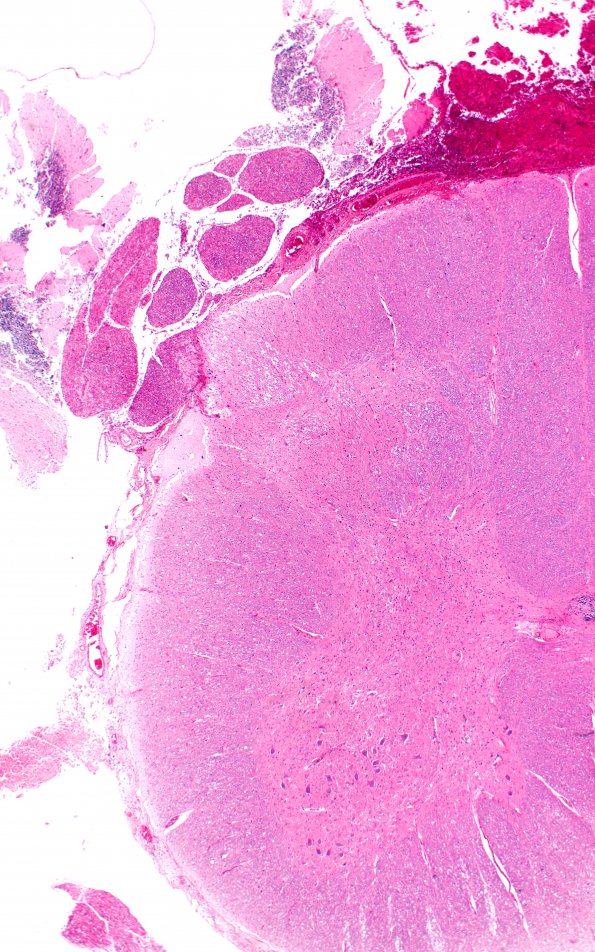

1B2 Autolysis, Cerebellum, necrotic in lumbosacral SAS (Case 1) H&E 2

Higher magnification view of image #1B1. (H&E)